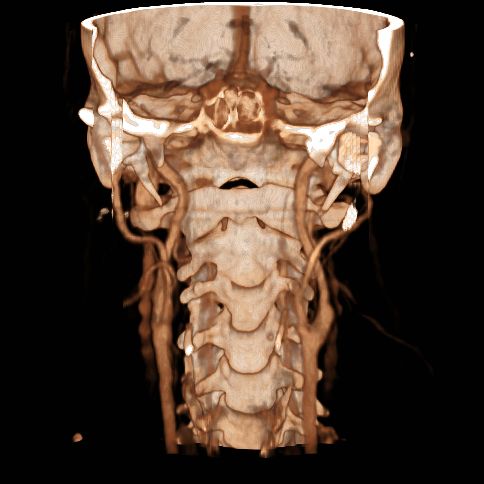

- analiza vasculaturii capului și a gâtului, incluzând arcul aortic și emergențele arterelor cervicale;

Evidențierea imagistică completă a arborelui arterial de la arcul aortic până la vertex în evaluarea atât a ocluziilor acute, cât si a stenozelor cronice poate fi realizată în timpul încărcării maxime cu contrast (peak).

Angiografia CT în afecțiunile arteriale extracraniene:

Angiografia CT și RM sunt minim invazive (se evită complicațiile inerente cateterizării invazive), sunt mai rapide și mai ieftine decât angiografia RX tradițională.